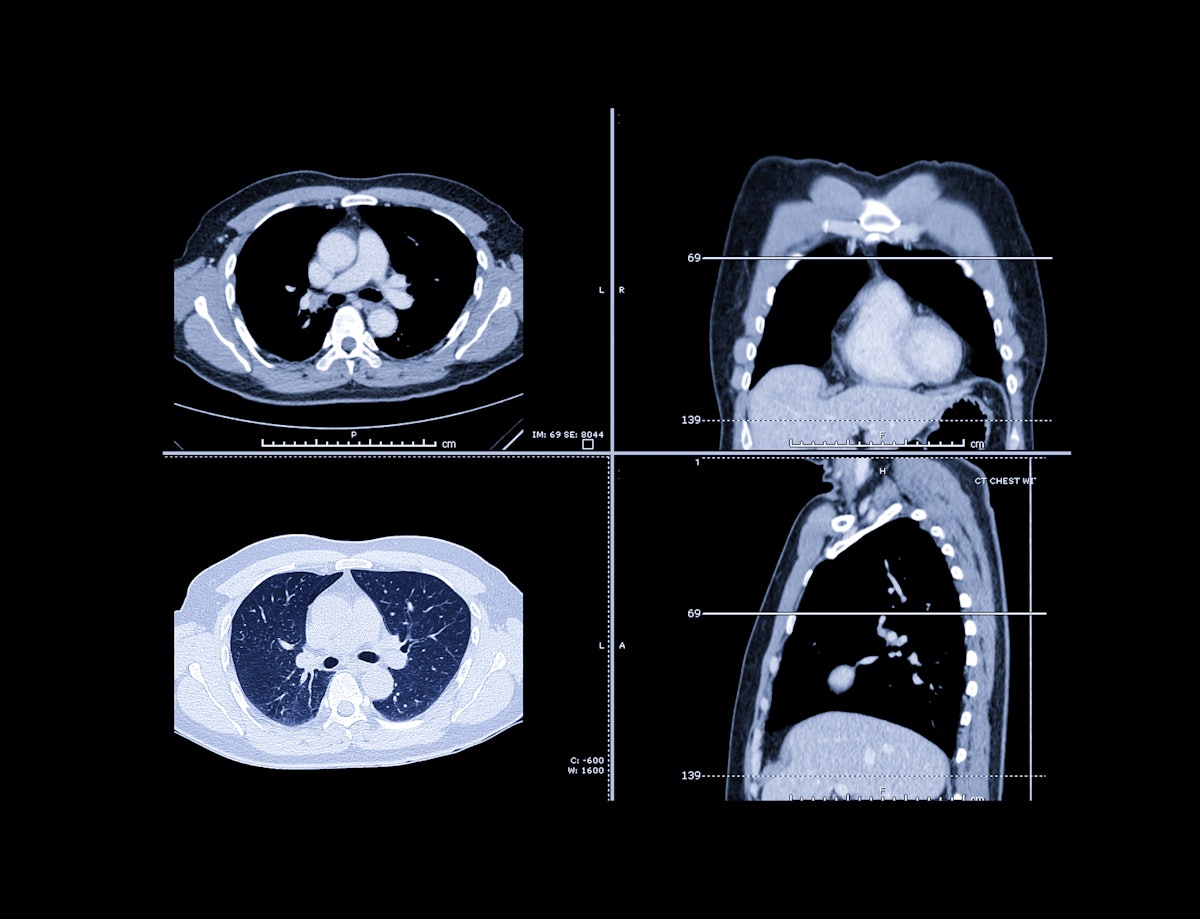

Cutting-Edge Technology: A New Era for Lung Cancer Diagnosis - Florida Hospital News and Healthcare Report

Positive LCS exams more common in national population than in NLST